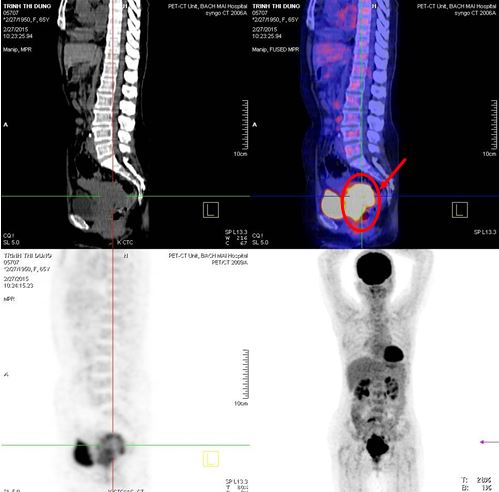

Chụp PET/CT:

-          Khối u vùng cổ tử cung (phía sau bàng quang) kích thước 5,7x6,1x7,6 cm tăng hấp thu FDG, max SUV = 10,88

-          Hai hạch chậu phải KT 2,2 cm tăng hấp thu FDG, max SUV = 6,81 và 2 cm tăng hấp thu FDG, max SUV 8,86

Hình 1. Hình ảnh PET/CT toàn thân: Khối u cổ tử cung kích thước lớn (mũi tên đỏ), hạch chậu phải (mũi tên vàng)

Chẩn đoán:Ung thư biểu mô tế bào vảy cổ tử cung T2N2M0, Giai đoạn: IIIb